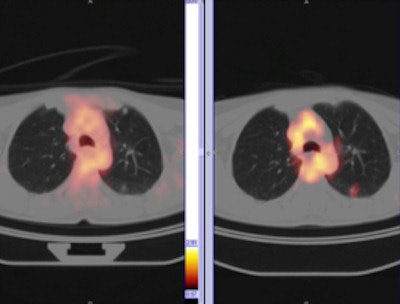

Pneumonitis induced by radiotherapy can cause increased uptake. Radiologists should know when radiotherapy treatment took place and the radiation doses administered. Increased uptake should be correlated with CT images to avoid making a false-negative diagnosis.